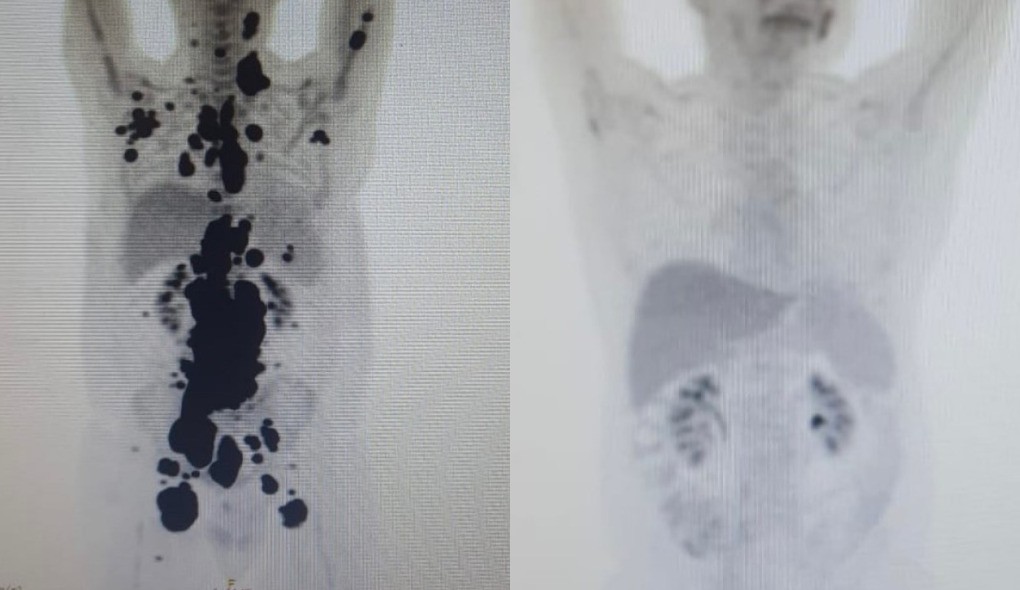

Paulo Peregrino, que lutava contra o linfoma há 13 anos, teve remissão completa em apenas um mês após receber o tratamento no Hospital das Clínicas de São Paulo. As imagens do PET Scan antes e depois mostram a redução drástica dos tumores, surpreendendo os médicos envolvidos.